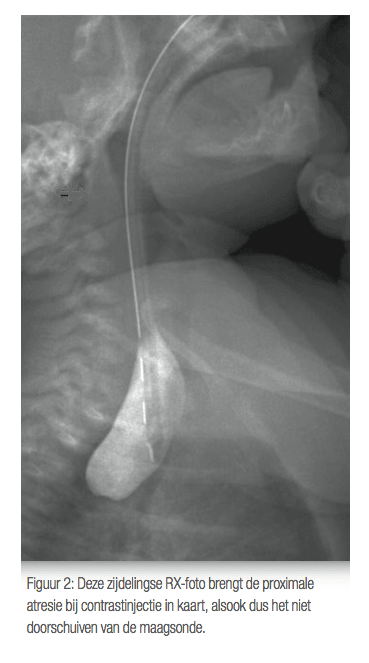

Un excès de liquide amniotique durant la grossesse (polyhydramnios) peut faire suspecter une atrésie œsophagienne avant la naissance. Dès les premières heures de vie, des signes évocateurs apparaissent : salivation abondante, difficultés à la tétée, voire rejet du biberon. Le diagnostic se confirme par radiographie à l’aide d’une sonde nasogastrique, qui s’enroule dans la partie haute de l’œsophage (voir Figure 2). Il est impératif d’orienter rapidement l’enfant vers une structure spécialisée avec unité néonatale.